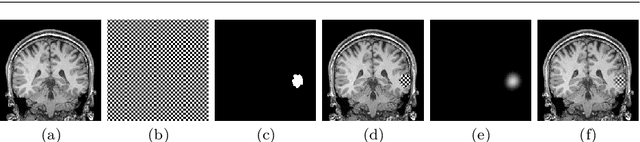

Abstract:Accurate segmentation of brain resection cavities (RCs) aids in postoperative analysis and determining follow-up treatment. Convolutional neural networks (CNNs) are the state-of-the-art image segmentation technique, but require large annotated datasets for training. Annotation of 3D medical images is time-consuming, requires highly-trained raters, and may suffer from high inter-rater variability. Self-supervised learning strategies can leverage unlabeled data for training. We developed an algorithm to simulate resections from preoperative magnetic resonance images (MRIs). We performed self-supervised training of a 3D CNN for RC segmentation using our simulation method. We curated EPISURG, a dataset comprising 430 postoperative and 268 preoperative MRIs from 430 refractory epilepsy patients who underwent resective neurosurgery. We fine-tuned our model on three small annotated datasets from different institutions and on the annotated images in EPISURG, comprising 20, 33, 19 and 133 subjects. The model trained on data with simulated resections obtained median (interquartile range) Dice score coefficients (DSCs) of 81.7 (16.4), 82.4 (36.4), 74.9 (24.2) and 80.5 (18.7) for each of the four datasets. After fine-tuning, DSCs were 89.2 (13.3), 84.1 (19.8), 80.2 (20.1) and 85.2 (10.8). For comparison, inter-rater agreement between human annotators from our previous study was 84.0 (9.9). We present a self-supervised learning strategy for 3D CNNs using simulated RCs to accurately segment real RCs on postoperative MRI. Our method generalizes well to data from different institutions, pathologies and modalities. Source code, segmentation models and the EPISURG dataset are available at https://github.com/fepegar/ressegijcars .